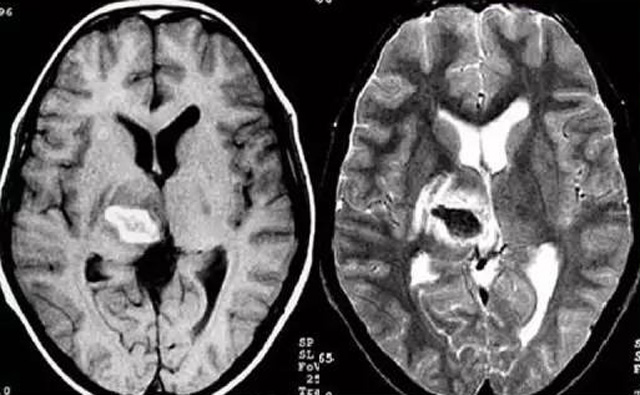

經(jīng)顱多普勒超聲(TCD)磁共振MRI檢查腦出血診斷的作用是什么?

發(fā)現(xiàn)病人出血腦梗相關(guān)癥狀時候第一時間就醫(yī),需要攜帶以往的影像檢查資料。向醫(yī)生提供相關(guān)的病史基本資料。做影像檢查時候需要全身不攜帶金屬物品。檢查時候身體保持不動,不然偽影對檢查結(jié)果有干擾。磁共振MRI發(fā)現(xiàn)缺血性卒中后,幫助進(jìn)一步查找病因。由于CT上小腦跟腦干顱骨影響,容易導(dǎo)致漏診。MRI檢查可以對CT檢查不足的補(bǔ)充。短暫的腦缺血TIA也需要進(jìn)行影像檢查。短暫性缺血一般10幾分鐘后好轉(zhuǎn)。檢查目的可以確定TIA的病因。降低腦梗死的發(fā)生率。磁共振有助于排出TIA表現(xiàn)的顱內(nèi)病變,有診斷及時治療的價值。磁共振MRI檢查時間比較長,不太適合急診病人。但是可以發(fā)現(xiàn)腦干小腦的出血問題。因?yàn)榧毙阅X梗死的早期和急性期,缺血區(qū)的腦組織還沒有完全壞死,頭顱CT不能顯示病灶,所以就需要MRI磁共振檢查,這個對陳舊跟亞急性出血顯示比較好。缺點(diǎn)性價比不高,費(fèi)用比較貴。頭顱的磁共振MRI在發(fā)病后的幾天CT的敏感降低時候發(fā)揮大作用。,MRI可作為診斷蛛網(wǎng)膜下腔出血和了解破裂動脈瘤部位的一種重要方法,必要時進(jìn)一步進(jìn)行DSA檢查,幫助制訂臨床的手術(shù)治療方案,

經(jīng)顱多普勒超聲(TCD)有效沒有創(chuàng)傷性的檢查方法,是檢查腦血管的設(shè)備之一,它目前廣泛應(yīng)用于臨床,檢查判斷腦出血卒中的頭顱里面的內(nèi)動脈外動脈的病變問題。診斷顱內(nèi)動脈狹窄或閉塞性病變。顱外頸部動脈狹窄或閉塞性病變,評價顱外動脈嚴(yán)重狹窄或閉塞對顱內(nèi)血流速度的影響。頸動脈內(nèi)膜剝脫手術(shù)前預(yù)測夾閉作用、術(shù)后評估顱內(nèi)血流變化。